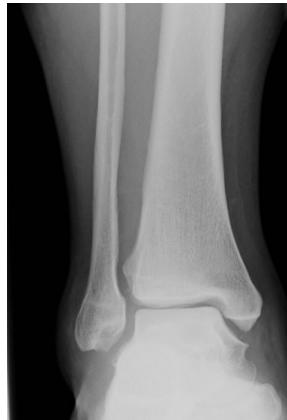

X-ray ap lat closed ,distal tibia extra-articular fracture, complete (two cortex), no articulation involvement, spiral (if two views appear broken), oblique (if one view) Oblique fracture, slight gapping (should be displaced if so), cortex appear normal, minimally displacement, angulation, rotation.

OLD ACID Framework

O - Open vs Closed

L - Location

D - Degree (complete vs incomplete)

A - Articulation involvement

C - Comminution & Pattern (type)

I - Intrinsic bone quality (cortex)

D - Displacement, angulation (distal to proximal), & rotation